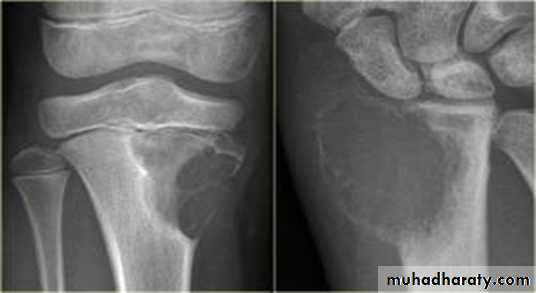

Giant cell tumor:Slowly growing , locally invasive, rarely metastasize.

Age: after closure of epiphysis (20-40 years).

Site: around knee & wrist joints.

Findings:

lytic, expansile lesion,

Sub articular in location,

Not clearly defined margin,

thinning of the cortex (sometimes with destruction of cortex)